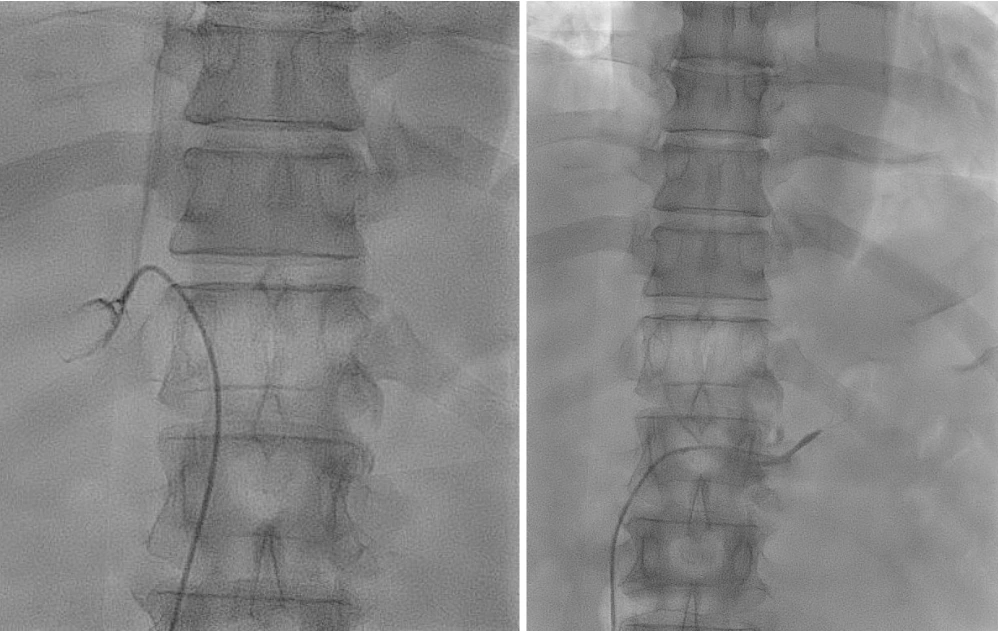

캡처.PNG

캡처1.PNG

사진 출처 : 강북 삼성병원 블로그

보통 시술은 30분~1시간 정도 걸린단다.

아주 가는 관이 부신 정맥까지 도달하는 꽤나 까다로운 과정이라고.

예를 들어, 혈관 주사를 놓을 때도 혈관을 찾기 위해 팔에 고무줄로 묶고 여기저기 누르면서 찾는다.

그런데 대퇴 정맥을 통해 몸 한가운데 가장 깊은 곳에 손톱만 한 크기로 달려있는 부신까지 도달, 부신 정맥을 채취하는 일이 어디 쉽겠는가?